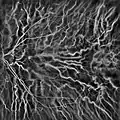

Schematic cross section of the human eye; choroid is shown in purple. Laser Doppler imaging of retinal and choroidal blood flow

Laser Doppler imaging of retinal and choroidal blood flow Iris, front view